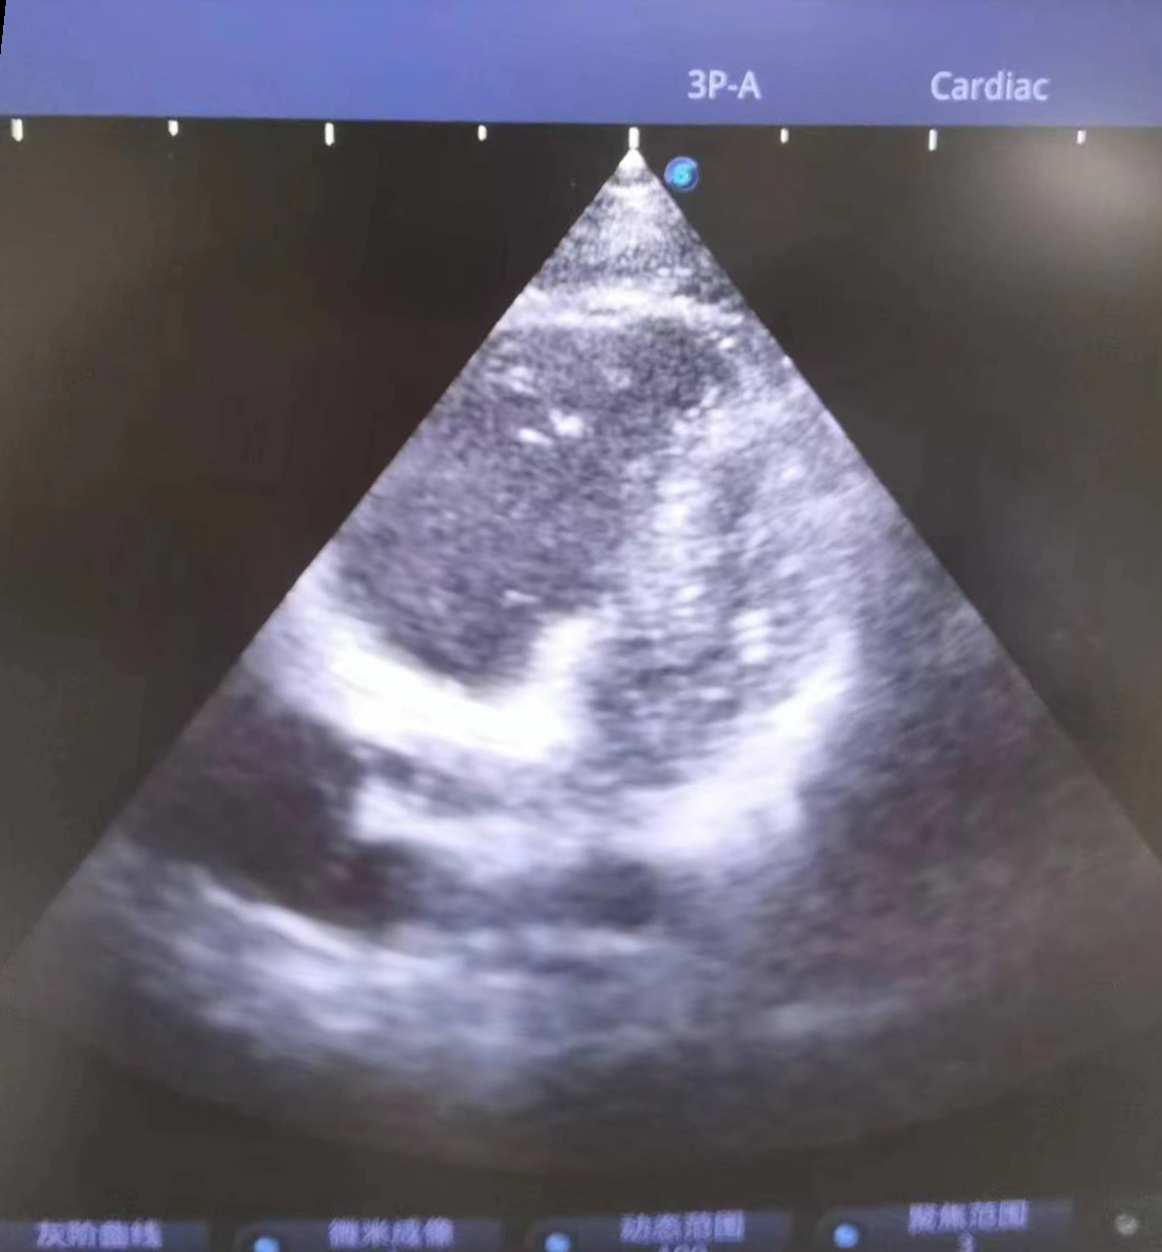

当天9点25分,小杨被送至急诊科,此时他面色苍白、呼吸困难、烦躁不安,无法配合治疗。急诊科医护紧急给予对症治疗,同时联系重症医学科(ICU)、心血管内科、超声影像科专家会诊。9点35分,小杨突然丧失意识,双侧瞳孔散大、心跳呼吸暂停,急诊科联合ICU医生立即行胸外心脏按压,呼吸球囊辅助呼吸,气管插管等抢救措施,因病情尚未明确,ICU医师紧急联系超声科医生行床旁心脏超声,心脏各切面均可见右心急性扩张,胸骨旁短轴切面可见左心室明显“D字征”,根据病人临床表现及超声检查,高度可疑为“急性大面积肺栓塞”,追问患者朋友,进一步了解到患者近日有下肢疼痛感,且既往有下肢骨折史,进而超声发现患者右下肢多处血栓形成。明确诊断后,阳逻院区院长、心血管内科学科带头人杨波当机立断给予阿替普酶治疗,为患者紧急溶栓。持续近一个小时的心肺复苏和溶栓治疗将小杨从死神手里拉了回来,10点14分,小杨心跳、呼吸恢复。

患者心脏彩超呈D字征,提示肺动脉高压,肺栓塞可能

患者彩超检查报告